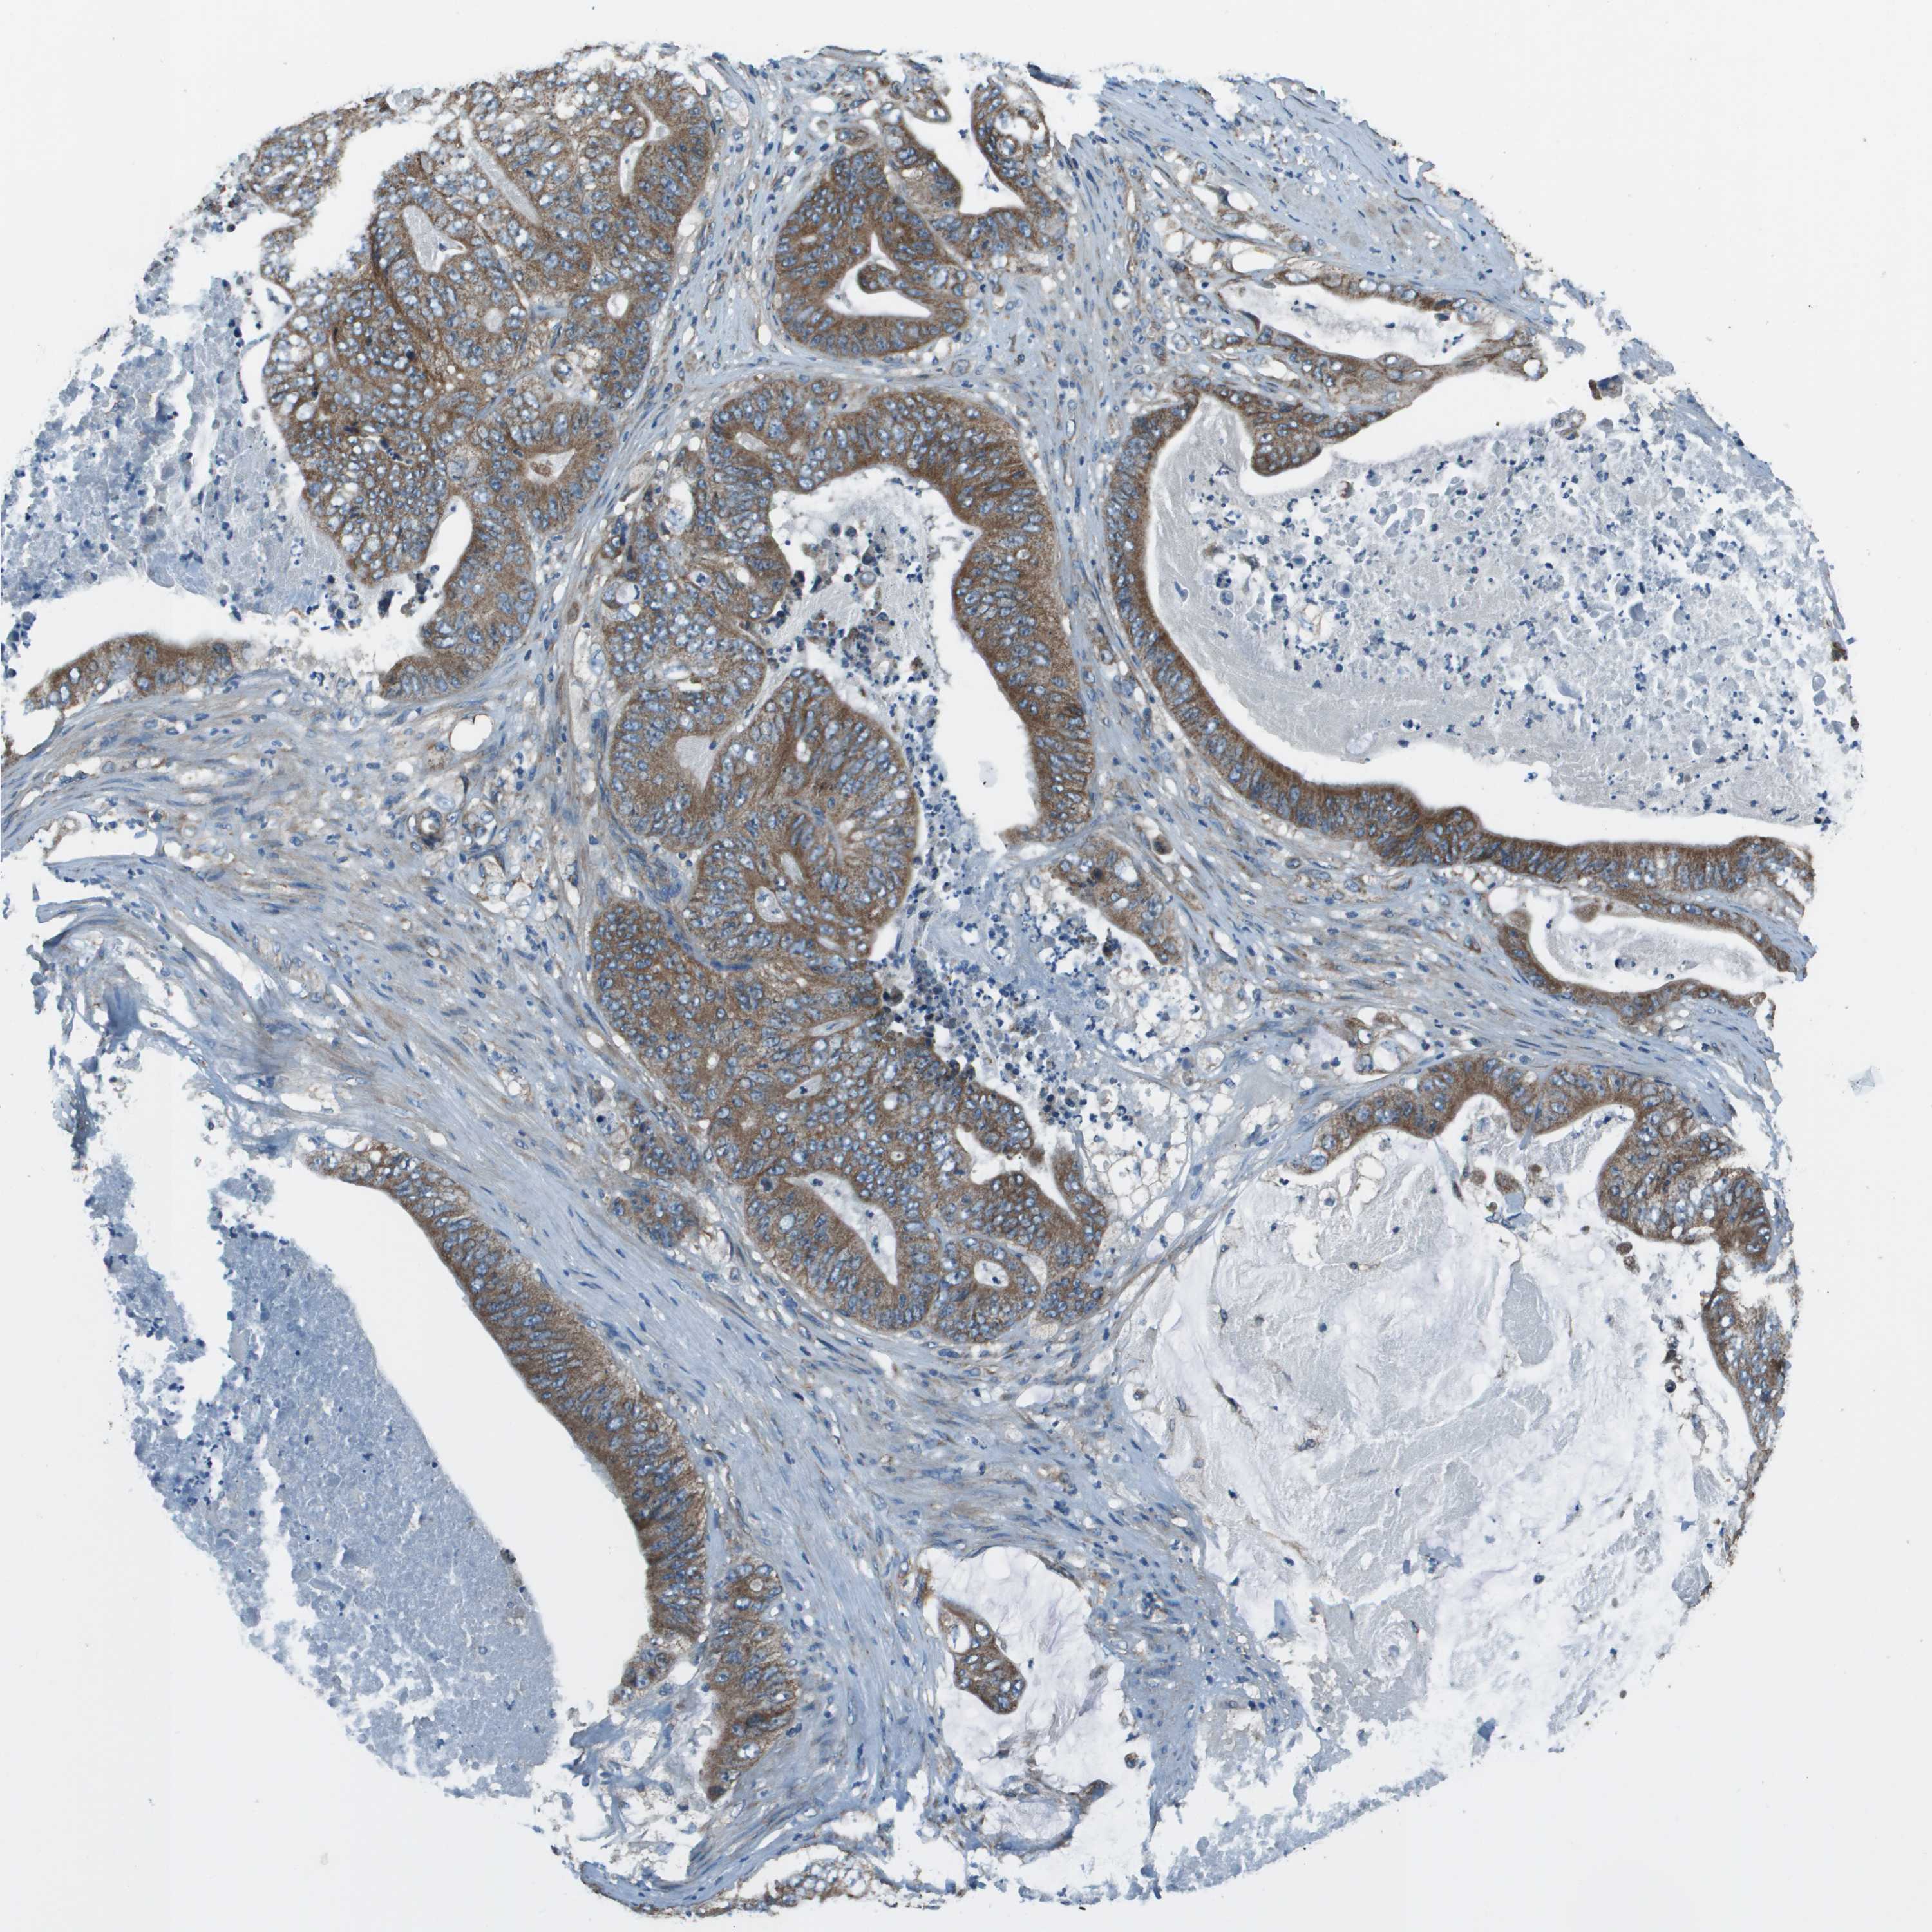

STOMACH CANCER - Protein expressioni

A mouse-over function shows sample information and annotation data. Click on an image to view it in a full screen mode. Samples can be filtered based on level of antibody staining by selecting one or several of the following categories: high, medium, low and not detected. The assay and annotation is described here.

Note that samples used for immunohistochemistry by the Human Protein Atlas do not correspond to samples in the TCGA dataset.

Antibody stainingi

Antibody staining in the annotated cell types in the current human tissue is reported as not detected, low, medium, or high, based on conventional immunohistochemistry profiling in selected tissues. This score is based on the combination of the staining intensity and fraction of stained cells.

Each image is clickable and will lead to virtual microscopy that enables deeper exploration of all samples and also displays staining intensity scores, fraction scores and subcellular localization as well as patient and tissue information for each sample.

Antibody HPA014547

Staining

High

Medium

Low

Not detected

Intensity

Strong

Moderate

Weak

Negative

Quantity

>75%

75%-25%

<25%

None

Location

Nuclear

Cytoplasmic/membranous

Cytoplasmic/membranous,nuclear

Adenocarcinoma, NOS